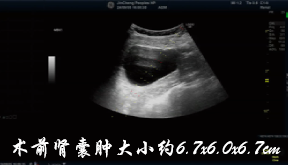

除了甲状腺囊肿,以下囊肿也适用微创硬化术: